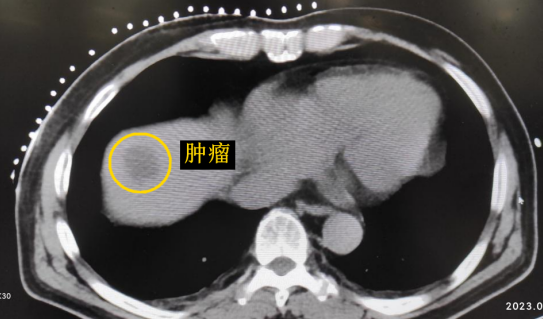

患者老年男性,曾于2021年行結(jié)腸癌手術(shù)。幾月前,發(fā)現(xiàn)肝臟轉(zhuǎn)移瘤,但沒(méi)有干預(yù)。近期CT顯示該轉(zhuǎn)移瘤明顯增大,并發(fā)現(xiàn)另一處轉(zhuǎn)移灶。

影像診療科陳寶瑩主任團(tuán)隊(duì)評(píng)估后指出,較大的腫瘤位于肝頂部緊貼膈肌,如果繼續(xù)發(fā)展,腫瘤很可能突破肝包膜侵犯到膈肌,建議及時(shí)干預(yù)。病變緊臨膈肌,如果要完全消融,膈肌損傷的可能性就比較大,與其他局部治療方式比較,冷凍消融對(duì)周?chē)K器、血管及神經(jīng)損傷的可能性較小、安全性更高、患者疼痛感較輕,建議通過(guò)CT精準(zhǔn)引導(dǎo)下經(jīng)皮微創(chuàng)冷凍消融治療。

CT精準(zhǔn)定位腫瘤